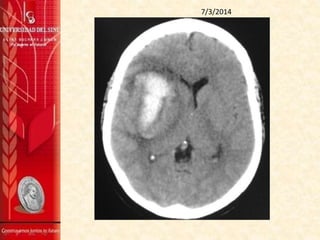

TAC DE CRÁNEO SIN CONTRASTE 27/2/2014

Se aprecia gran hematoma intraparenquimatoso

comprometiendo la región ganglio basal derecha, parte del

lóbulo frontal y temporal del mismo lado, sus contornos son

irregulares y sus diámetros máximos del plano axial son de 59

mm (AP) x 27 mm (TRV). Sus características están a favor de

una etiología hipertensiva entre otros diagnósticos

diferenciales.

La línea media está desviada hacia la izquierda

aproximadamente 6 mm por el efecto de masa producido por

el hematoma, y colapsa casi totalmente el ventrículo lateral

derecho.

No se aprecian alteraciones en la fosa posterior.

IMPRESIÓN:

1. Hematoma intraparenquimatoso comprometiendo la

región ganglio-basal derecha, parte del lóbulo frontal y

temporal del mismo, muy probablemente de origen

hipertensivo.